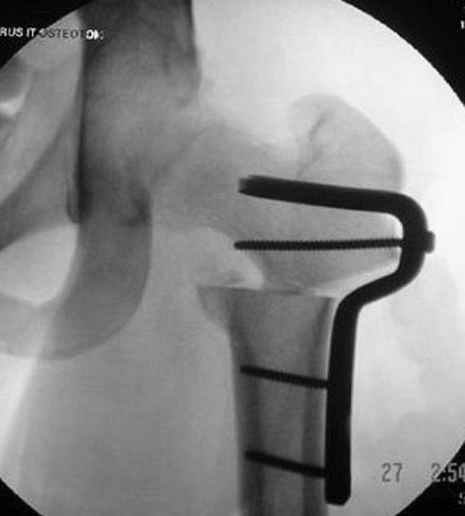

7:30 начало операции, больной на спине, попытка репозиции после анестезии N3, укладка больного на боку, доступ Kocher- Langenbeck, состояние седалищнего нерва около 2.5см кровоподтек, через joistick головка бедра приподнята, освобовождение сустава, фрагмент заднего края более 3х4 см репонирован на свое место. После промывания

сустава, репозиция вывиха (N4), фиксация фрагмента 2.7(4) мм шурупами и допольнительно реконструктивной пластиной на 8 дырок, фиксация 3.5мм шурупами проксимально и дистально.

Интраоперционные N5 косая запирательная и N6 подвздошный снимок